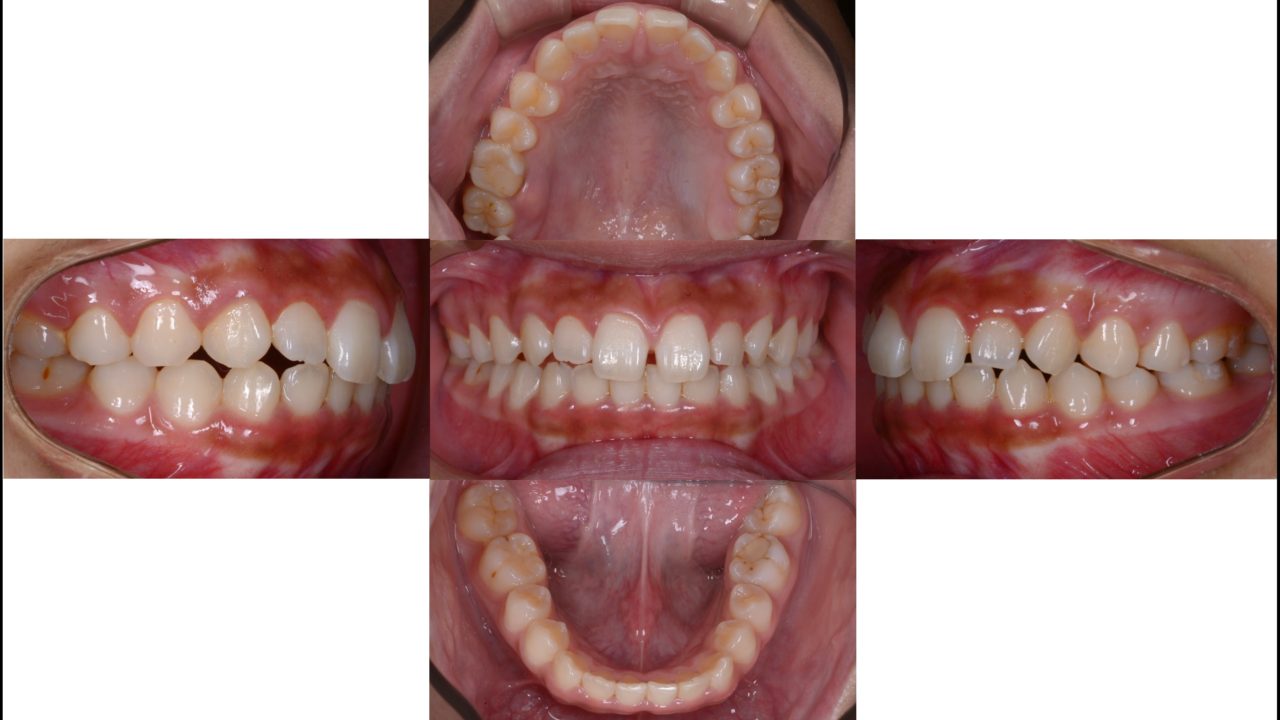

2020.12.9 初診

初診レントゲン

2021.1.7 矯正治療開始